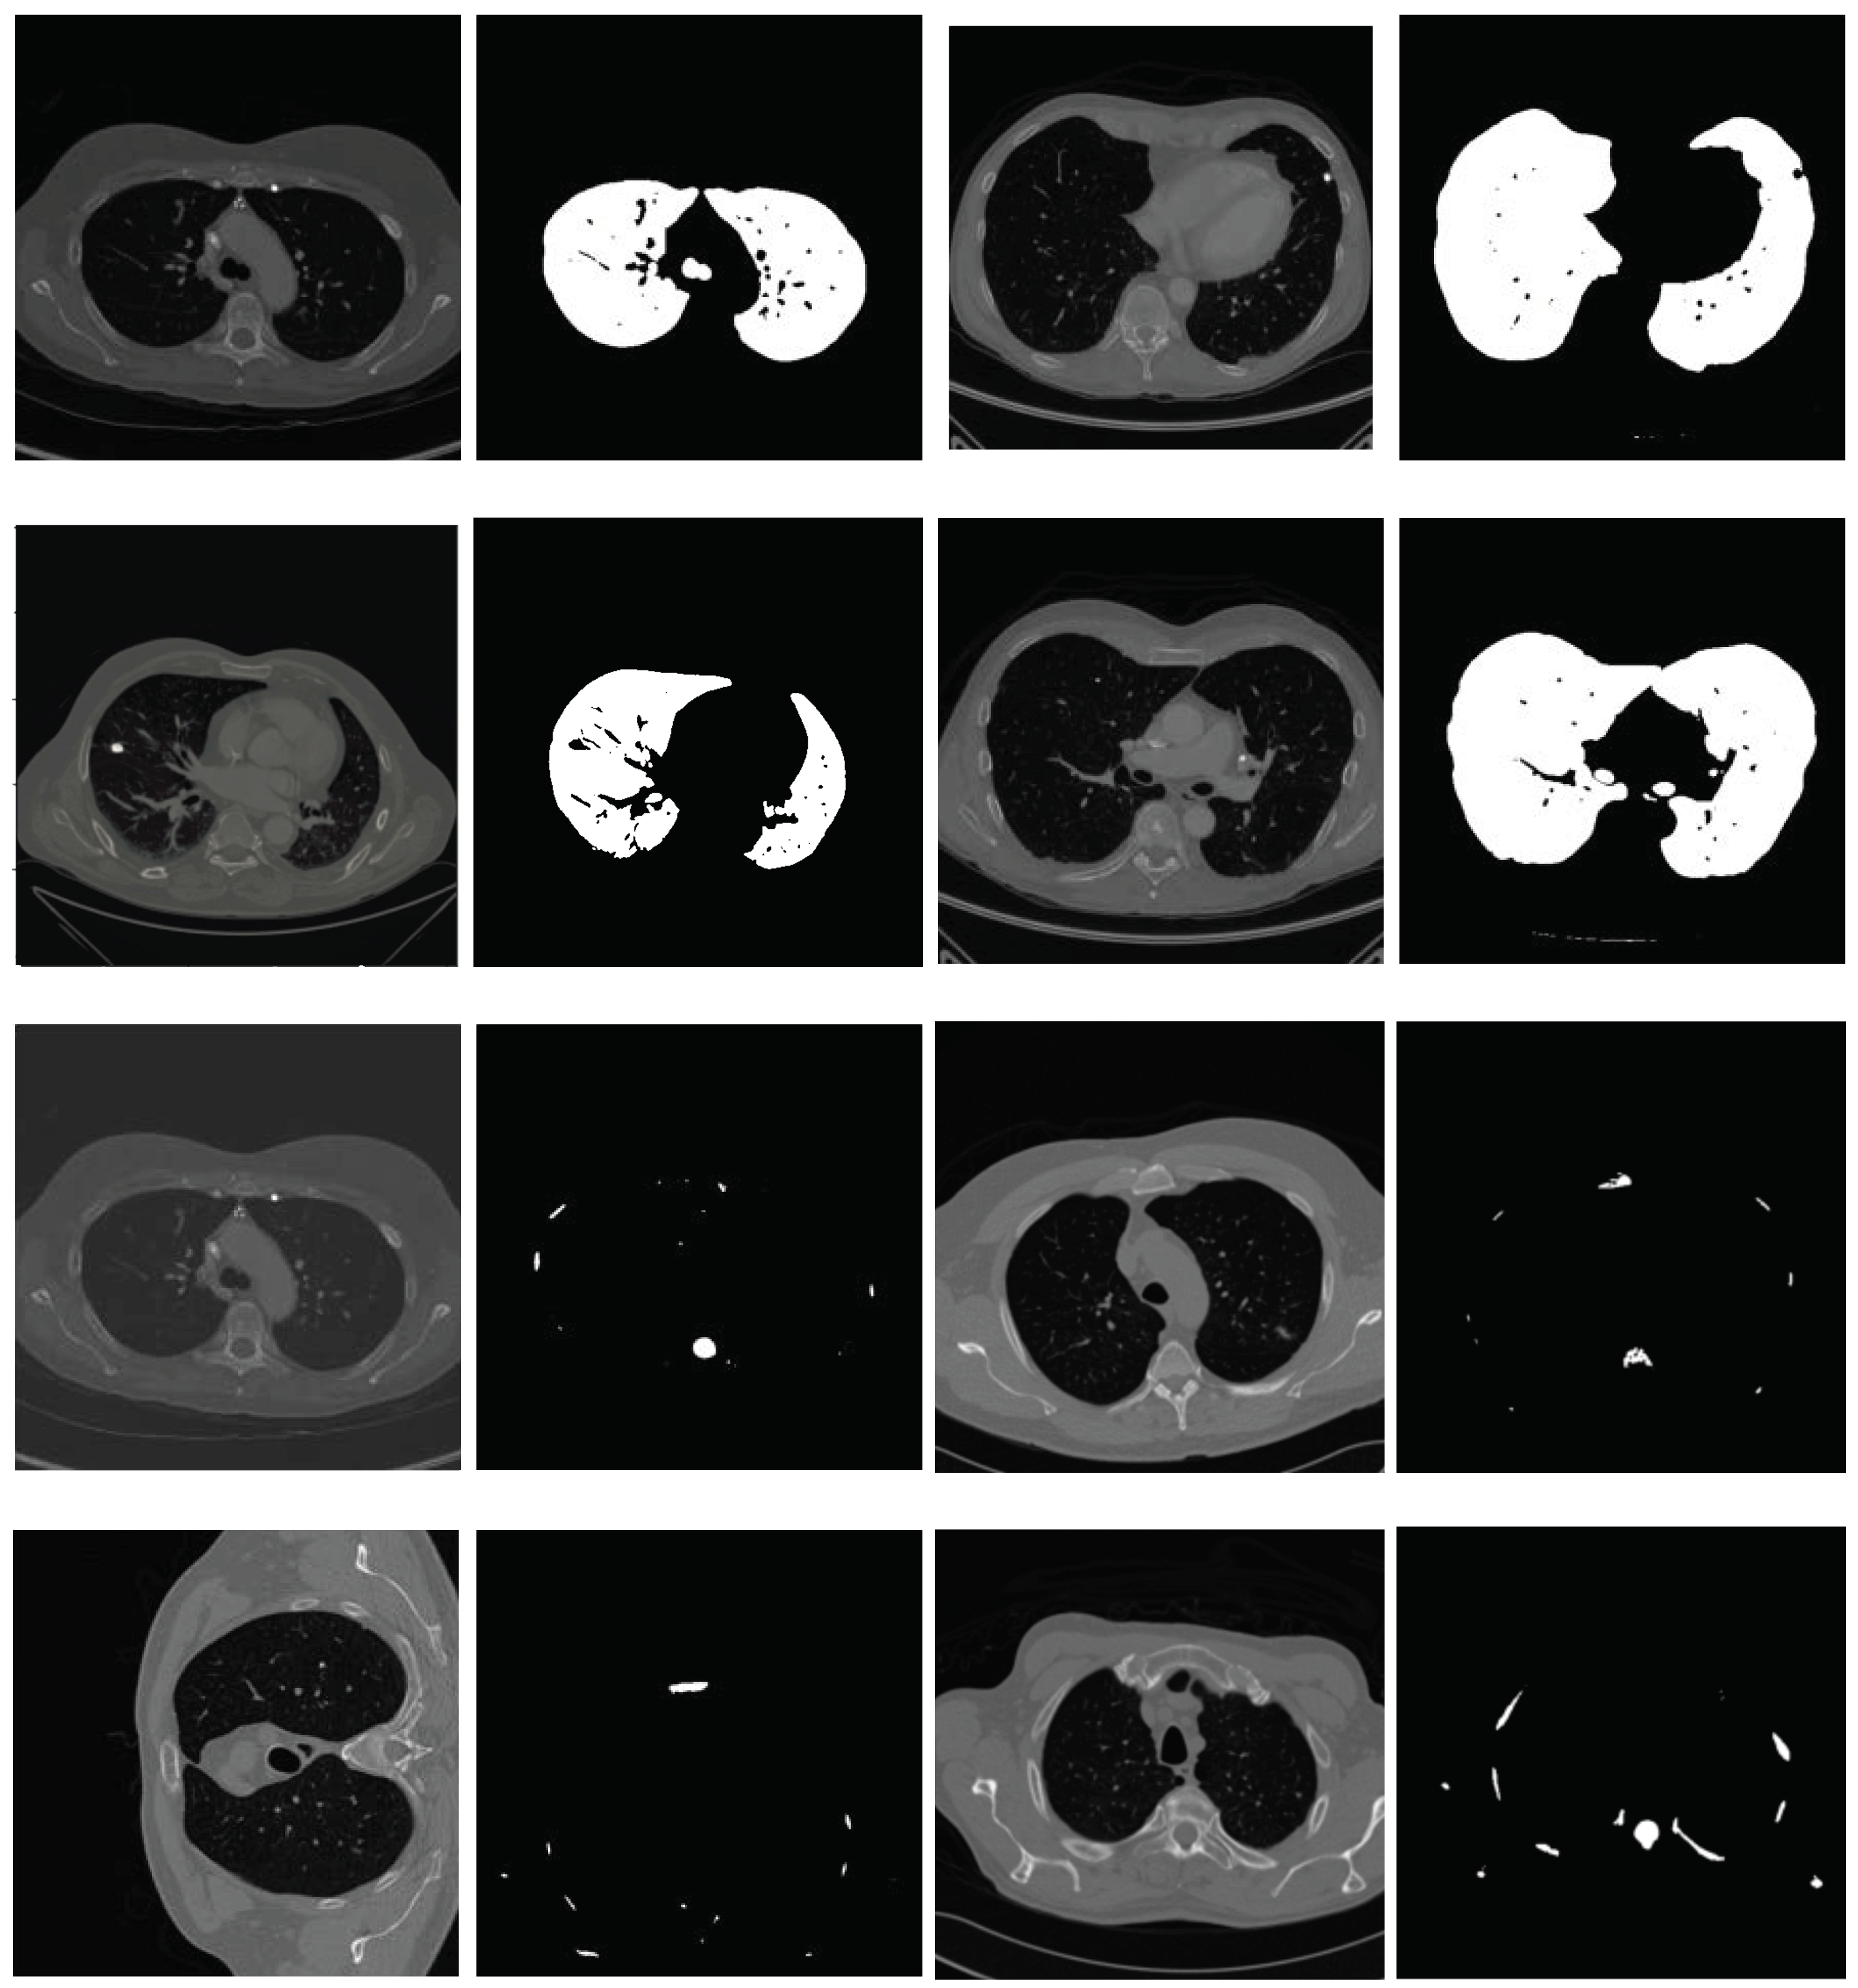

After the lungs are segmented, the next step is the extraction of vessels from the lungs. We achieve this by simply applying thresholding to the segmented lungs. The intensity levels of objects inside the lungs are lower than the lung background. We observe that a threshold value −500 is a good choice to extract vessels and nodules from the segmented lungs, as shown in Figure 8a. Following vessel extraction, morphological techniques, namely binary opening and binary closing, are used to eliminate the smaller objects from the area. We calculate the region of all the objects included in the vessel mask. Almost all nodules are circular, with white pixels covering most of the circle. As a result, we can disregard the additional objects with the elongation feature. We compute the diameter of each lesion to detect the nodule. The diameter threshold that we set to detect nodules is 3 mm because, in our dataset, the radiologists annotated the nodules within the range of 3–30 mm and this is the general nodule size in lung cancer. A few radiologists considered a nodule size of 2 mm but they later disregarded these annotations [41]. Figure 8c shows the nodule detected using the extracted nodule candidates (shown in Figure 8b). Figure 8d shows the detected nodule in the original image. The pseudocode of the proposed algorithm is presented in Algorithm 1.

Figure 8.

(a) Segmented lungs, (b) extracted nodule, (c) nodule mask, (d) corresponding original image with nodule highlighted in red circle.